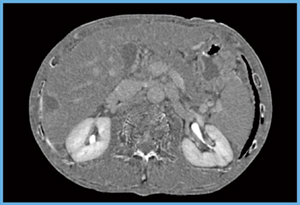

肝ダイナミックCTのプロトコールは,造影剤総量600mgl/kgを30秒間静注し,管電圧120kVで単純相,動脈優位相,門脈優位相,平衡相の4相を撮影。平衡相に関しては4分で撮影している。ECV mapは,SURESubtraction Iodine Mappingによるサブトラクション画像にヘマトクリット値と大動脈のCT値を入力して作成するソフトウエアを利用した。図1がSURESubtraction Iodine Mappingから作成したECV mapだが,特に軟部組織(臓器)で,ミスレジストレーションの少ないサブトラクションが実現していることがわかる。

図1 SURESubtraction Iodine Mappingを用いたECV map